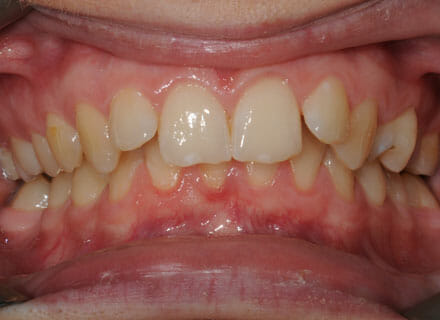

This lady came to us because she was unhappy with her crooked, uneven teeth.

The front ones were sticking out and she didn’t like her overbite. we were to move all the teeth sticking out back to where they should be, at the same time we made all the teeth nice and straight.

Treatment duration: about 12 months.

Brace Type: clear brackets